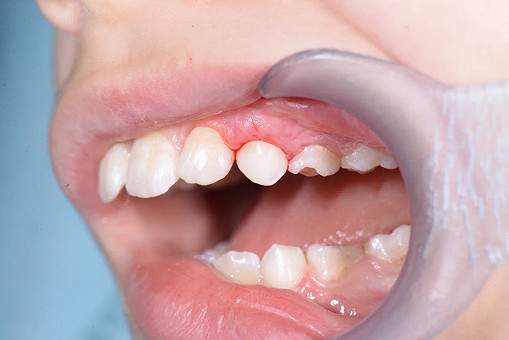

До/после лечения